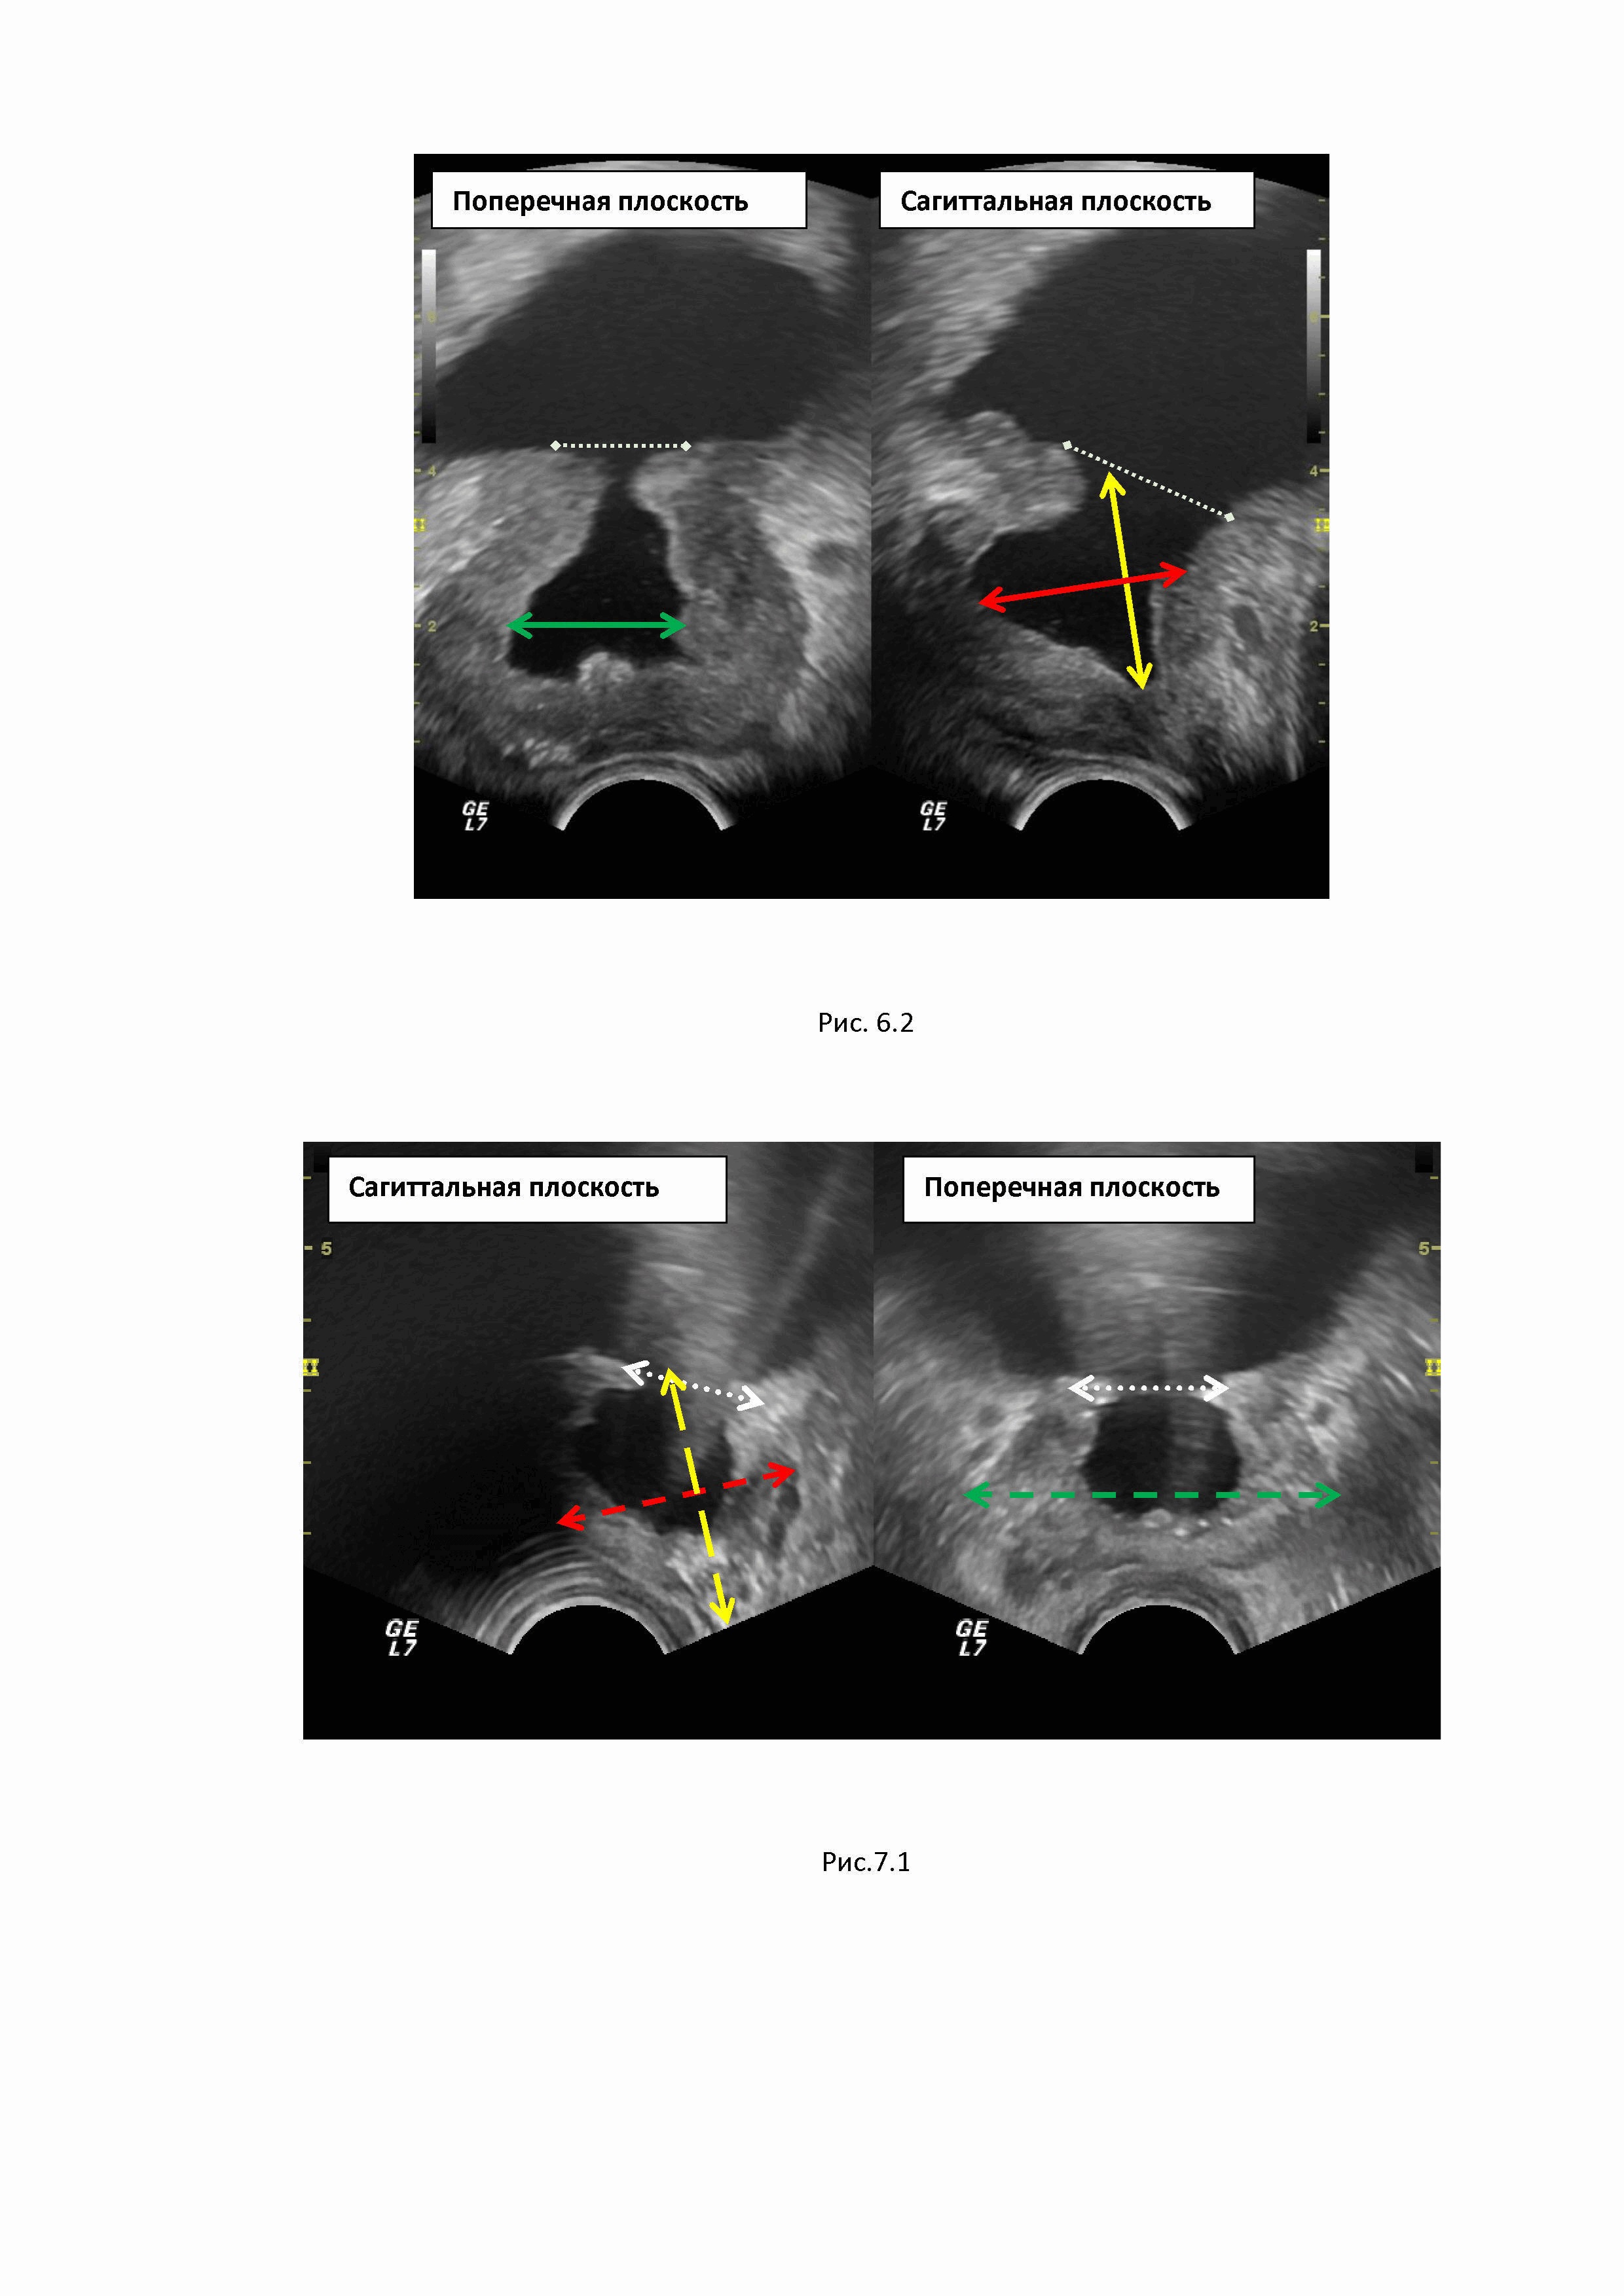

Изобретение относится к области медицины, в частности к ультразвуковой диагностике, и предназначено для улучшения количественной оценки остаточного объема ткани предстательной железы после ее резекции. Способ обеспечивает получение количественных показателей остаточного объема ткани резецированной простаты, что позволит вычислять плотность ПСА, значение которого в настоящее время расцениваются как один из надежных предикторов ранней диагностики рака простаты при динамическом наблюдении за больным. Точность измерения объема предстательной железы (простаты) приобрела принципиальную важность благодаря результатам последних исследований, в ходе которых было установлено, что наибольшей корреляцией среди лабораторных показателей и вероятностью рака простаты обладает показатель плотности ПСА (10, 12). Плотность ПСА рассчитывается как отношение значения исходной концентрации сывороточного общего ПСА к объему предстательной железы (2, 11, 13), а именно: где ПСА-D – плотность ПСА (от английского «PSA density»), На сегодняшний день именно плотность ПСА признается большинством экспертов одним из самых надежных прогностических критериев диагностики рака предстательной железы (РПЖ). При этом пороговым значением ПСА-D считается уровень 0,151 нг / мл / см3 (5). Однако у большой части мужчин старшей возрастной группы предстательная железа увеличивается в размерах, что требует хирургического лечения. Патологоанатомические изменения преимущественно наблюдаются в центральных отделах простаты, где формируется аденоматозная трансформация ткани (гиперпазия простаты, или аденома простаты). Аденоматозная ткань занимает центральную часть предстательной железы и деформирует шейку мочевого пузыря. Это приводит к формированию клинических проявлений аденомы простаты – дизурических жалоб и, что самое главное, к формированию нарушения опорожнения мочевого пузыря, которое, в конечном итоге, может стать причиной развития уремии. Исторически известен метод хирургического лечения данного состояния – чрезпузырная аденомэктомия по Федорову–Фрейеру. Аденомэктомия по Федорову-Фрейеру, несмотря на множество других предложенных методов лечения, относится к основным и наиболее радикальным методам лечения аденомы предстательной железы (1, 8). Несмотря на многочисленные модификации, техника данного оперативного вмешательства остается прежней (7, 9). При операции Федорова-Фрейера аденоматозные ткани удаляются вместе с пузырно-уретральным сегментом и предстательным отделом уретры одним блоком. В ходе операции образуется свободная полость в центральной части простаты, так называемый предпузырь, и его объем соответствует массе удаленных тканей простаты. При этом образуется тканевой дефект, соответствующий по форме эллипсу, диаметром от 3 см, а иссеченный край мочевого пузыря является границей его ложа. Боковыми и задней стенками служат остаточные ткани простаты, нижняя граница предпузыря располагается на уровне семенного бугорка (6). Проблема определения остаточного объема резецированной предстательной железы связана с отсутствием объективной формулы для подсчета объема железы в послеоперационном периоде по причине изменения ее конфигурации после хирургического лечения. На рис.1 представлены этапы трансуретральной резекции центральной части простаты (аденомэктомии): 1.1. Резектоскоп введен в уретру. 1.2. Этап удаления аденоматозной ткани в центральной части простаты. 1.3. Завершение операции с формированием остаточной полости (предпузыря) и сохранением периферической части простаты. Имеющиеся формулы подсчета объема неоперированной железы подразумевают форму простаты, близкую к объемному эллипсу. После проведения резекции конфигурация простаты меняется за счет удаления ткани в ее центральных отделах и формирования предпузыря округлой формы, что не позволяет объективно измерить объем органа. Известный способ определения объема простаты с использованием ультразвуковой диагностики (4) и МРТ (3, 5). При проведении магнитно-резонансной томографии малого таза определение размеров предстательной железы является необходимым условием, помимо указания её размеров современные тенденции требуют и определения объёма простаты. Для определения размеров железы используются Т2-взвешенные изображения (Т2-ВИ), за счёт высокой контрастности полученных изображений, что позволяет чётко дифференцировать анатомические границы железы (3). Измерения производят в двух взаимно перпендикулярных плоскостях: сагиттальной и аксиальной (или поперечной) (рис.2). Границы и срезы выбираются в каждом случае врачом-рентгенологом индивидуально в зависимости от формы железы, её анатомических особенностей, выраженности гиперпластических изменений в транзиторной зоне. В сагиттальной плоскости от основания до апекса простаты измеряются ее продольной размер (А), в средней трети железы измеряются передне-задний размер железы (В), а поперечной плоскости измеряют ширину простаты (С). Согласно рекомендациям PI-RADS v2.1, измерение объема предстательной железы ПЖ проводится вручную на основе формулы объема эллипсоида или с помощью автоматических алгоритмов измерения объема (5). V простаты =А х В х С х 0.523, где А – продольный размер, В – переднезадний размер, С – ширина простаты, 0.523 – поправочный коэффициент для вычисления объема эллипсоида. Использование единого подхода к расчету объема предстательной железы с помощью формулы объема эллипсоида имеет особое значение. В PI-RADS v2.1 рекомендуют измерение максимального переднезаднего размера и перпендикулярного к нему продольного размера на срединных сагиттальных T2-ВИ, а максимальную ширину рекомендуют измерять на поперечных срезах в T2-ВИ (5). При проведении УЗИ простаты с целью измерения объема ПЖ также традиционно используют формулу измерения объема эллипсоида (4) V простаты =А х В х С х 0,523, где А – продольный размер простаты, В – передне-задний размер, С – ширина простаты в средней трети, 0.523 – поправочный коэффициент (14). Ультразвуковое исследование проводят в двух взаимоперпендикулярных плоскостях – сагиттальной и поперечной. В саггитальной плоскости измеряют продольный размер простаты от основания простаты до апекса железы (А), в этой же плоскости перпендикулярно продольному размеру в средней трети железы измеряют передне-задний размер (В). Далее перемещают датчик в поперечную плоскость и в средней части железы производят измерение ширины железы С, проводя измерительную дистанцию от боковых границ органа. На рис.3 представлен алгоритм измерения объема неоперированной простаты при проведении трансректального УЗИ в двух плоскостях сагиттальной и поперечной. В сагиттальной плоскости сканирования от основания до апекса железы желтым пунктиром обозначен продольный размер (А). В этой же плоскости красный пунктир, проведенный от передней границы до задней границы железы, соответствует передне-заднему размеру. В поперечной плоскости сканирования зеленый пунктир, проведенный от правой боковой до левой боковой границы простаты, соответствует ширине железы (С) в средней трети железы. После проведения резекции при хирургическом лечении аденомы простаты конфигурация простаты меняется за счет удаления ткани в ее центральных отделах, поскольку на месте удаленной ткани в центральных части железы формируется предпузырь округлой формы, что не позволяет объективно измерить объем органа. На рис.4 представлено ультразвуковое изображение, демонстрирующее остаточный, объем резецированной простаты и изменение конфигурации железы за счет формирования предпузыря на месте удаленной аденоматозной ткани (объем предпузыря обозначен белой стрелкой). Указаний на необходимость измерения предпузыря после резекции простаты методом УЗД или МРТ в доступной литературе нам не встретилось. В руководстве «Магнитно-резонансная томография предстательной железы» под ред. А.В. Мищенко дается описательная характеристика предпузыря как воронкообразного дефекта аденоматозно-измененной простаты без метрических показателей (3). В тоже время точность измерения объема приобрела принципиальную важность в последние годы благодаря результатам последних исследований, в которых была продемонстрирована значимость критерия плотности ПСА в сыворотке крови (в нг/мл), рассчитываемой как соотношение сывороточного ПСА к объему предстательной железы (11,13). На сегодняшний день именно плотность ПСА признается большинством экспертов одним из самых надежных прогностических критериев диагностики РПЖ. Технической проблемой, на решение которой направлено изобретение является разработка достоверного и простого способа определения остаточного объема резецированной простаты после аденомэктомии. Техническим результатом разработанного способа является объективизация значения остаточного объема резецированной простаты, что позволит корректно измерять плотность ПСА в остаточном объеме резецированного органа по формуле (11,13) где ПСА-D – плотность ПСА (от английского «PSA density»), Способ определения остаточного объема резецированной простаты характеризуется тем, что проводят трансректальное ультразвуковое исследование простаты, при котором последовательно производится измерение простаты целиком с целью определения объема железы, включая объем предпузыря, на следующем этапе проводят измерение и вычисление объема предпузыря, и, путем вычитания объема предпузыря из объема простаты, измеренного целиком, получают остаточный объем резецированной простаты. При осуществлении способа проводят трансректальное исследование. С этой целью микроконвексный ультразвуковой датчик частотой 7 – 9 МГц вводят в ампулу прямой кишки, предварительно изолировав его поверхность резиновым ультразвуковым наконечником для соблюдения асептики. Проводят детальную оценку предстательной железы и предпузыря. Далее приступают к проведению измерения простаты и предпузыря с целью получения показателей объема обеих структур. Измерение объема резецированной простаты целиком получают при измерении трех линейных параметров – продольного (А), передне-заднего (В) размеров и ширины ПЖ(С). На рис.5.1 представлено измерение объема резецированной простаты целиком, включая объем предпузыря. Измерение размеров производится последовательно в сагиттальной и поперечной плоскостях сканирования. В сагиттальной плоскости (левое фото) проводится желтый пунктир от границы предпузыря (белый пунктир) до апекса простаты. Граница предпузыря маркируется виртуальной замыкающей линией, от которой измерительный маркер направляется к верхушке простаты. Данный размер соответствует продольному размеру простаты А. Желтый пунктир, соответствующий передне-заднему размеру железы (В), проводится в этой же плоскости от передней к задней границе простаты. Далее измерение производится в поперечной плоскости сканирования простаты, для чего датчик размещают перпендикулярно первоначальной дистанции. В поперечной плоскости (правое фото) зеленый пунктир, проведенный от боковых границ железы, соответствует ширине простаты в средней трети железы (С). Измерение ширина простаты производят на уровне средней части простаты. На основании полученных показателей по известной формуле (4) вычисляют объем простаты вместе с предпузырем (целиком): Vпростаты целиком = А х В х С х 0,523, где А – продольный размер простаты, см, В – передне-задний размер простаты, см, С – ширина простаты, см, 0.523 – поправочный коэффициент. Второй этап. Далее приступают к измерению объема полости предпузыря. Для этого проводят линейные измерения в двух плоскостях – сагиттальной и поперечной - и получают значения продольного (a), передне-заднего (b) размеров и ширины (c) предпузыря. Продольный размер измеряют в сагиттальной плоскости, проводя измерительный маркер от замыкающей верхние границы предпузыря виртуальной линии до нижней границы предпузыря с простатой на уровне семенного бугорка. В этой же плоскости сканирования измеряют передне-задний размер предпузыря, для чего перпендикулярно к первой линии проводят измерительный маркер спереди назад по передне-задним границам предпузыря в его средней трети. Ширина предпузыря изменяется в средней части объекта в поперечной плоскости сканирования железы. На рисунке 5.2 представлено измерение объема предпузыря. От верхней границы предпузыря (белая пунктирная линия – виртуальная граница простаты в зоне резекции) проводится сплошная желтая линия до нижней границы предпузыря, что соответствует продольному размеру. Красная сплошная линия, проведенная также в сагиттальной плоскости, от передней до задней границы полости предпузыря, соответствует передне-заднему размеру. Далее датчик располагают в перпендикулярной плоскости сканирования, и получают изображение железы в поперечной плоскости. Сплошная зеленая линия, проведенная от боковых границ полости предпузыря, соответствует его ширине. На основании полученных показателей вычисляют объем предпузыря по формуле вычисления объема эллипсоида (4): Vпредпузыря = a х b х c х 0,523, где а – продольный размер предпузыря, b – передне-задний размер предпузыря, с – ширина предпузыря, 0.523 – поправочный коэффициент. Третий этап. Вычисление остаточного объема резецированной простаты. На основании проведенных измерений вычисляют остаточный объем резецированной простаты (V резецированной простаты) Vрезецированной простаты = Vпростаты целиком –Vпредпузыря или Vрезецированной простаты = (А х В х С х 0,523)– a х b х c х 0,523) Полученная величина является основой для измерения плотности ПСА-D (11,13), измерение которой проводиться по известной формуле где ПСА-D – плотность ПСА, нг/мл/см³, ПСА общ. – значения общего ПСА, нг/мл, Vост. – остаточный объем резецированной простаты, см3. Установление количественных показателей остаточного объема ткани резецированной простаты позволяет вычислять плотность ПСА. Значение плотности ПСА получают как соотношение показателя ПСА в нг/мл к объему остаточной ткани резецированной простаты в куб.см. Значение плотности ПСА в настоящее время рассматривается как важнейший фактор при динамическом наблюдении пациентов при онконасторженности (5). При получение значений ПСА-D более 0.151 пациент должен рассматриваться как потенциальный больной раком простаты с проведением стандартизированного онкологического исследования (МКБ Z03.1 Наблюдение пациента с подозрением на злокачественное новообразование). В связи с этим количественная оценка остаточного объема резецированной простаты является важнейшим условием выбора тактики ведения больного. Невозможность провести объективное измерение объема простаты после резекции традиционным способом связано с существенным изменением формы железы после операции, что не позволяет использовать в клинической практике показатель «плотность ПСА», важность которого доказана в онкоурологии. Невозможность использования в клинической практике достоверного показателя уровня плотности ПСА может привести к ложному представлению о состояния больного и выбору ошибочной тактики. Клинические примеры: №1 Больной П., 65 лет. Наблюдается урологом. Пять лет назад перенес резекцию простаты (трансуретральную аденомэктомию). ПСА в динамике 1.3 нг/мл - 2.2 нг/мл - 1.8 нг/мл. В настоящий момент ПСА 5.21 нг/мл. Жалоб активно не предъявляет. Результаты УЗИ: рис. 6.1. На первом этапе в сагиттальной плоскости измеряли объем простаты (вместе с предпузырем), для чего в сагиттальной плоскости от виртуальной границы зоны резекции мочевого пузыря (белый пунктир) проводили измерительную дистанцию до верхушки простаты (дистанция обозначена желтым пунктиром) и получили значение 4.2 см. Далее в этой же плоскости сканирования средней трети простаты проводили измерительную дистанцию перпендикулярно первому измерению от передней до задней границы железы (дистанция обозначена красным пунктиром) с получением результата 4.2 см. Далее переходили в поперечную плоскость сканирования простаты, для чего разворачивали датчик перпендикулярно предыдущему положению. Измерение ширины простаты (дистанция обозначена зеленым пунктиром) проводили от правой до левой границы простаты в средней ее трети с получением результата 5.2 см. Далее производили вычисление объема простаты целиком с объемом предпузыря по известной формуле вычисления объема эллипсоида: V простаты целиком = 4.2 х 4.2 х 5.2 х 0.523 = 47.9 см3. Измерение объема предпузыря (рис.6.2) производили в двух плоскостях - сагиттальной и поперечной. Длинник измеряли в сагиттальной плоскости от виртуальной границы предпузыря с мочевым пузырем (белый пунктир) до нижней границы (желтая сплошная линия) с получением результата 2.4 см. В это же плоскости сканирования получали передне-задний размер предпузыря, проводя линию в средней части предпузыря от передней до задней его границы (красная сплошная линия) с получением результата 2.3 см. Измерение ширины предпузыря проводили в поперечной плоскости сканирования, изменив положение датчика на перпендикулярное начальному и проводя измерительный маркер от правой до левой границы предпузыря (зеленая сплошная линия) с получением результата 2.3 см. Далее вычисляли объем предпузыря по известной формуле объема эллипсоида: Vпредпузыря = 2.4 х 2.3 х 2.3 х 0.523= 6.6 см3. Остаточный объем резецированной простаты вычисляли путем вычитания объема предпузыря из объема простаты целиком с получением результата: Vрезецированной простаты =Vпростаты целиком –Vпредпузыря = 47.9 –6.6= 41.3 см3. Плотность ПСА (ПСА-D) вычисляли путем деления показателя ПСАобщ. в нг/мл на остаточный объем резецированной простаты (Vрезецированной простаты) в куб. см: ПСА-D = 5.21 нг/мл : 41.3 см3 = 0.126 нг/мл/ см3. Поскольку полученные результаты плотности ПСА соответствуют нормальному значению (норма до 0.151), больному было предложено динамическое наблюдение, за время которого данных за онкологический процесс выявлено не было. № 2 Больной Л., 72 лет. Двенадцать лет назад перенес радикальную аденомэктомию по поводу гиперплазии простаты. Динамически не наблюдался. В настоящее время обратился к урологу по поводу жалоб на умеренную болезненность при мочеиспускании. ПСА 3.83 нг/мл. С целью выявления патологии простаты проведено УЗИ. Определяли объем простаты целиком. С этой целью при проведении трансректального УЗ-сканирования сагиттальной плоскости (рис.7.1) проводили измерительный маркер (желтый пунктир) от виртуальной границы предпузыря с мочевым пузырем (белый пунктир) до верхушки простаты, получив значения длинника простаты 3.5 см. В этой же плоскости проводили измерение передне-заднего размера простаты, для чего проводили измерительный маркер (красный пунктир) от передней до задней границы простаты в средней трети органа с получением результата 3.3 см. Для измерения ширины простаты переводили датчик в перпендикулярное положение, и в поперечной плоскости сканирования на уровне средней трети простаты проводили измерительный маркер (зеленый пунктир) от правой до левой границы железы, получив результат 5.0 см. Объем простаты целиком (вместе с предпузырем) вычисляли по известной формуле объема эллипсоида: V простаты целиком = 3.5 х 3.3 х 5.0 х 0.523 = 30.2 куб.см. Объем предпузыря вычисляли в двух плоскостях (рис.7.2): длинник предпузыря и передне-задний размер пузыря получали при сканировании в сагиттальной плоскости. Для получения размера длинника проводили измерительный маркер (желтая сплошная линия) от виртуальной границы предпузыря (белый пунктир) до проекции нижней границы предпузыря (проекция семенного бугорка) с получением размера 2.6 см. Далее измеряли переднее-задний размер предпузыря, для этого измерительный маркер (красная сплошная линия) проводили перпендикулярно первой дистанции в направлении от передней до задней границы предпузыря с получением результата 2.2 см. Следующим этапом сканирования было получение показателя ширины предпузыря в поперечной плоскости сканирования железы. Для этого измерительный маркер (зеленая сплошная линия) проводили в средней части простаты от правой до левой границы предпузыря с получением результата 2.3 см. Вычисление объема предпузыря проводили по формуле объема эллипсоида: Vпредпузыря = 2.6 х 2.2 х 2.3 х 0.523=6.9 куб.см. Вычисление остаточного объема резецированной простаты проводили путем вычитания объема предпузыря из объема простаты целиком. Vрезецированной простаты = Vпростаты целиком - Vпредпузыря = 30.2 – 6.9 = 23.3 см3. Плотность ПСА вычисляли путем деления показателя ПСАобщ. в нг/мл на остаточный объем резецированной простаты (Vрезецированной простаты): ПСА-D=3.83 нг/мл : 23.3 куб.см = 0.164 нг/мл/см3. Полученный результат превышал допустимое значение (норма до 0.151), и пациенту был поставлен диагноз: Z03.1. Наблюдение пациента с подозрением на злокачественное новообразование, что потребовало развернутого онкологического обследования - была проведена компрессионная соноэластография, в левой доле выявлен очаг высокой ригидности, что свидетельствует о наличии злокачественного процесса. Выполненная МРТ подтвердила наличие патологического очага левой доли резецированной простаты. Проведена трансректальная пункционная биопсия под УЗ-наведением. По данным биопсии: аденокарцинома, Gleason sum 3+3= 6. Больной направлен на консультацию к урологу-онкологу для выработки дальнейшей тактики лечения. Литература 1. Доброкачественная гиперплазия предстательной железы. Под ред. Н.А. Лопаткина. М., 1997. 2. Кнеев А.Ю., Школьник М.И., Богомолов О.А., Вершинская Ю.Г., Жаринов Г.М. Плотность простатспецифического антигена как прогностический маркер у больных локализованным раком предстательной железы. Урологические ведомости. 2021, Том 11, № 3, стр. 205-212. 3. Магнитно-резонансная томография предстательной железы / Дубицкий Д., Мищенко А. В., Л., Трофименко И. А. – Москва: ГОЭТАР-Медиа, 2021. - 528 с. 4. Назаренко Г.И., Хитрова А.Н. Ультразвуковая диагностика предстательной железы в современной урологической практике. – Москва: Издательский дом «Видар-М», 2012. – 288 с. 5. Рубцова Н. А., Мищенко А. В., Данилов В. В., Гулин Г. А., Алексеев Б. Я., Каприн А. Д. PI-RADS v2.1: движение на пути к ясности (комментарии к обновленной версии). Онкоурология, 2020, № 2, т.16, стр. 151-28. 6. Сергиенко Н.Ф., Василенко М.И., Кудряшов О.И. Классическому радикальному экстрауретральному способу аденомэктомии более 30 лет», Урология. 2015, № 4, стр.39-43. 7. Сергиенко Н.Ф., Василенко М.И., Кудряшов О.И. К вопросу о так называемом «золотом стандарте» оперативного лечения аденомы предстательной железы. Урология, 2021, № 4, стр. 69-72. 8. Степанов В.Н. Симптоматика и клиническое течение доброкачественной гиперплазии предстательной железы. В кн.: Доброкачественная гиперплазии предстательной железы. Под ред. Н.А. Лопаткина. М., 1997. С. 41–45. 9. Урология: учебник/ Б.К. Комяков. М.: ГОЭТАР-Медицина, 2011. – стр.309-317. 10. Dong F. et al. Validation of pretreatment nomograms for predicting indolent prostate cancer: efficacy in contemporary urological practice. J Urol 2008;180:150. 11. Lee S.J., Oh Y.T., Jung D.C. et al. Combined analysis of biparametric MRI and prostate-specific antigen density: role in the prebiopsy diagnosis of Gleason score 7 or greater prostate cancer. AJR Am J Roentgenol 2018;211(3):W166–72. DOI: 10.2214/AJR.17.19253. 12. Loeb S. et al. Active surveillance for prostate cancer: a systematic review of clinicopathologic variables and biomarkers for risk stratification. Eur Urol 2015;67:619. 13. Mehralivand S., Shih J.H., Rais-Bahrami S. et al. A magnetic resonance maging-based prediction model for prostate biopsy risk stratification. JAMA Oncol 2018;4(5):678–85. DOI: 10.1001/jamaoncol.2017.5667 14. Terris M.K., Stamey T.A. Detrmination of prostate volume by transrectal ultrasound. J.Urol.1991; 145 (5);984-987.